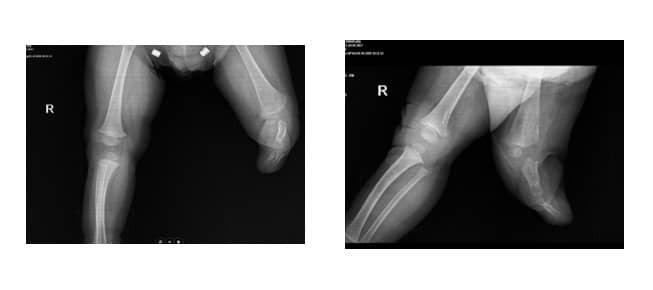

На нашата клиника беше насочено 7-месечно момче поради тежка деформация на лявото стъпало. Установено бе отсъствие на 5-ти лъч на десния крак, дефект на три реда и талипес еквиноварус на левия крак (Фиг. 11 А, В). Семейната анамнеза беше отрицателна за аномалии на крайниците. Пациентът имаше нормален квадрицепсен сухожилие и патела.

Фиг. 11. А. Клинични снимки на засегнатата страна

B. Рентгенови снимки на засегнатата страна

При детското проследяване не беше извършена хирургична намеса от дясната страна. Обхватът на сгъване в лявото коляно беше оценен на 50 градуса. Това дете активно използваше протеза под коляното и нямаше оплаквания (Фиг. 12 А, В).

Фиг. 12. Рентгенови снимки 2 години след операцията

А. Антеропостериорен рентген

В. Латерален рентген